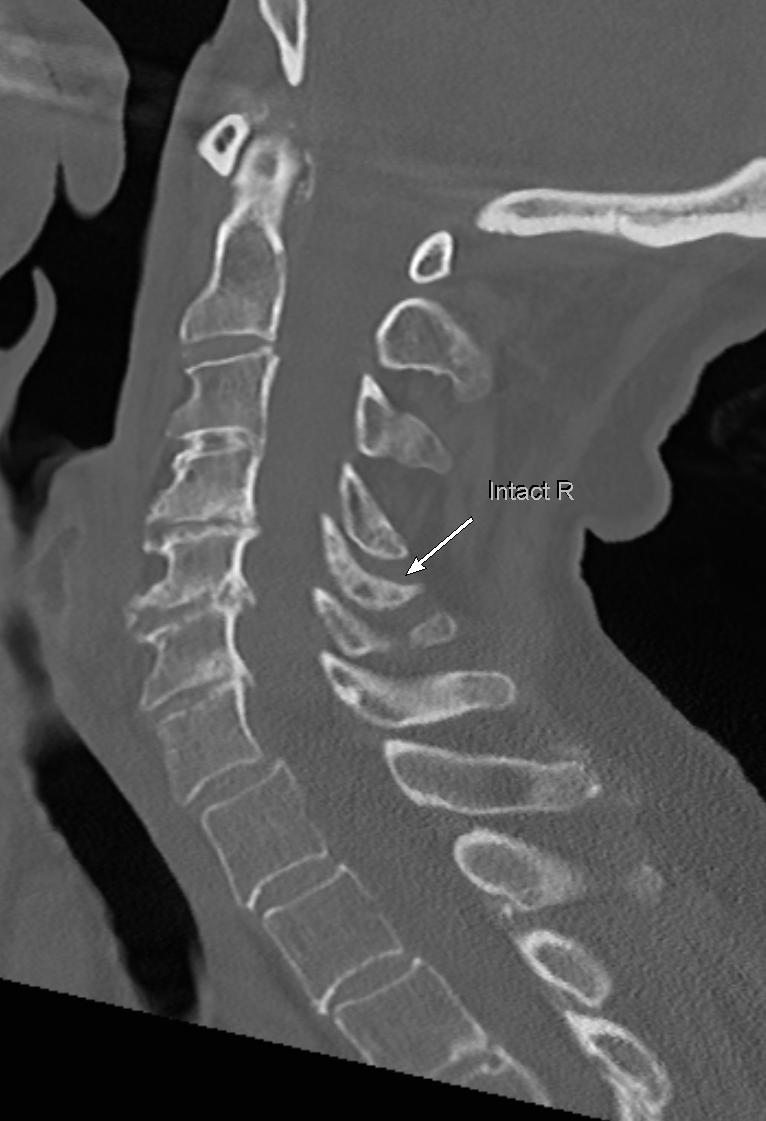

Non displaced trabecular compression fractures are

#easytomiss in osteoporotic#spine;#radres please review soft tissue window for such fractures-surrounding sclerosis due to edema/hemorrhage/compression can make them more visible#FOAMed@NASSspine https://bit.ly/37XAAdH pic.twitter.com/1oGrDA6jz6